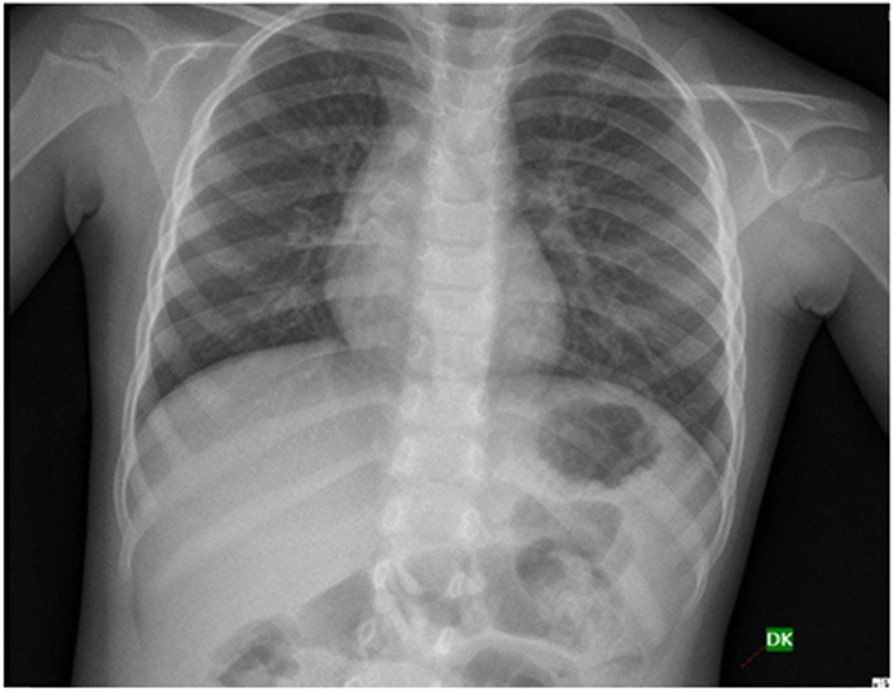

Fig. 4From: Clinical variables responsible for early and late diagnosis of foreign body aspiration in pediatrics age groupNormal Chest x-ray in a case of early FBABack to article page